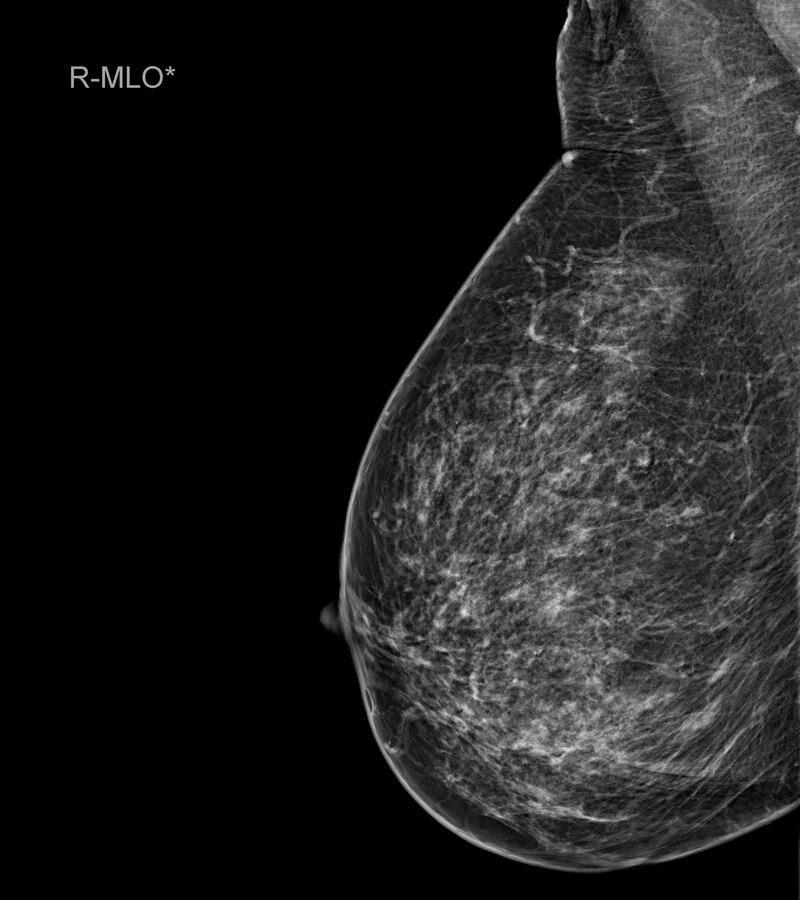

¿Qué es una mamografía?

“Una mamografía es una imagen de la mama tomada con rayos X que permite ver una imagen del interior de los senos. Existen mamografías de detección y mamografías de diagnóstico. Al realizarse una mamografía como especialista puedo detectar irregularidades en la mama o tumores que aún no se pueden sentir”, cuenta Clayreth Vinueza especialista en radiología.

Para la experta una mamografía debe realizarse a partir de los 40 años una vez todos los años. Además, que en mujeres con antecedentes de cáncer de mama o de varios se recomienda comenzar antes.